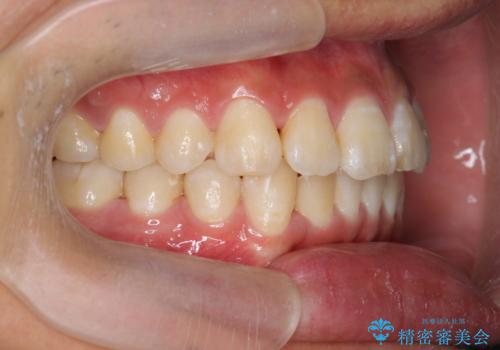

遠心移動を伴うマウスピース非抜歯矯正治療

- 「前歯の見た目を改善したい。」と矯正治療を希望され来院されました。

前歯のガタつきに加え、上顎が前にある咬合関係(上顎前突)を改善すべく、マイクロインプラントを用いた上顎奥歯の後方移動、拡大、ディスキングを用いたマウスピース矯正治療を計画します。

マイクロインプラントを使用したことで、しっかりと遠心移動が為され、良好な咬合関係が達成されました。